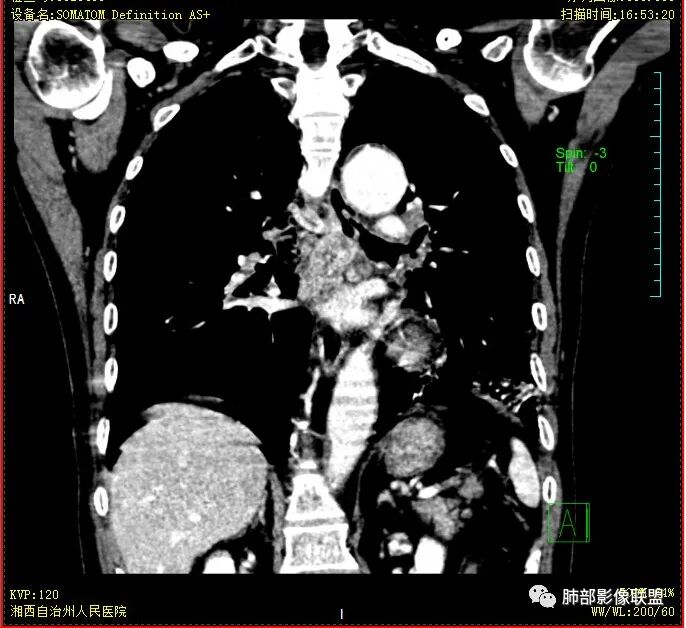

双肺多发结节影,树芽征,小叶中心分布,左肺下叶不规则空洞,洞内壁光滑,见液平,洞壁似与支气管相通,增强扫描明显强化,可见血管造影征。三周左右复查空洞明显缩小。

双肺多发点片、索条斑条灶,见多发树丫征,左下肺大片不均质实变,内见一含气液平厚壁空洞,壁厚,内壁有坏死物残留,增强可空洞壁明显强化

,空洞位于肺门侧,近端支气管壁不规则增厚。

胸部CT:双肺多发小斑片、树芽、索条灶,左下肺大片不均质实变,远肺门侧厚壁空洞,气液平,内壁有坏死物残留,增强可空洞壁不均匀强化,近端支气管壁不规则增厚堵塞,实变影内可见与洞壁平行支气管。抗炎3周有缩小。

3.注意到左肺下叶空洞性病灶,腔壁厚度不均,环形强化较为明显,壁间支气管血管影走行,腔内液气平面,这通常见于感染性病灶,如脓肿,经治疗病灶吸收也高度支持病灶主体成分为脓肿。

4.老年男性患者,痰中带血,体重减轻,空洞性病灶壁厚不均疑及肿瘤性病变符合常理。

尽管坏死明显,但穿行血管结构自然,血供如此丰富,鳞癌的判断使人望而却步,腺癌的判断也缺乏有说服力的线索。